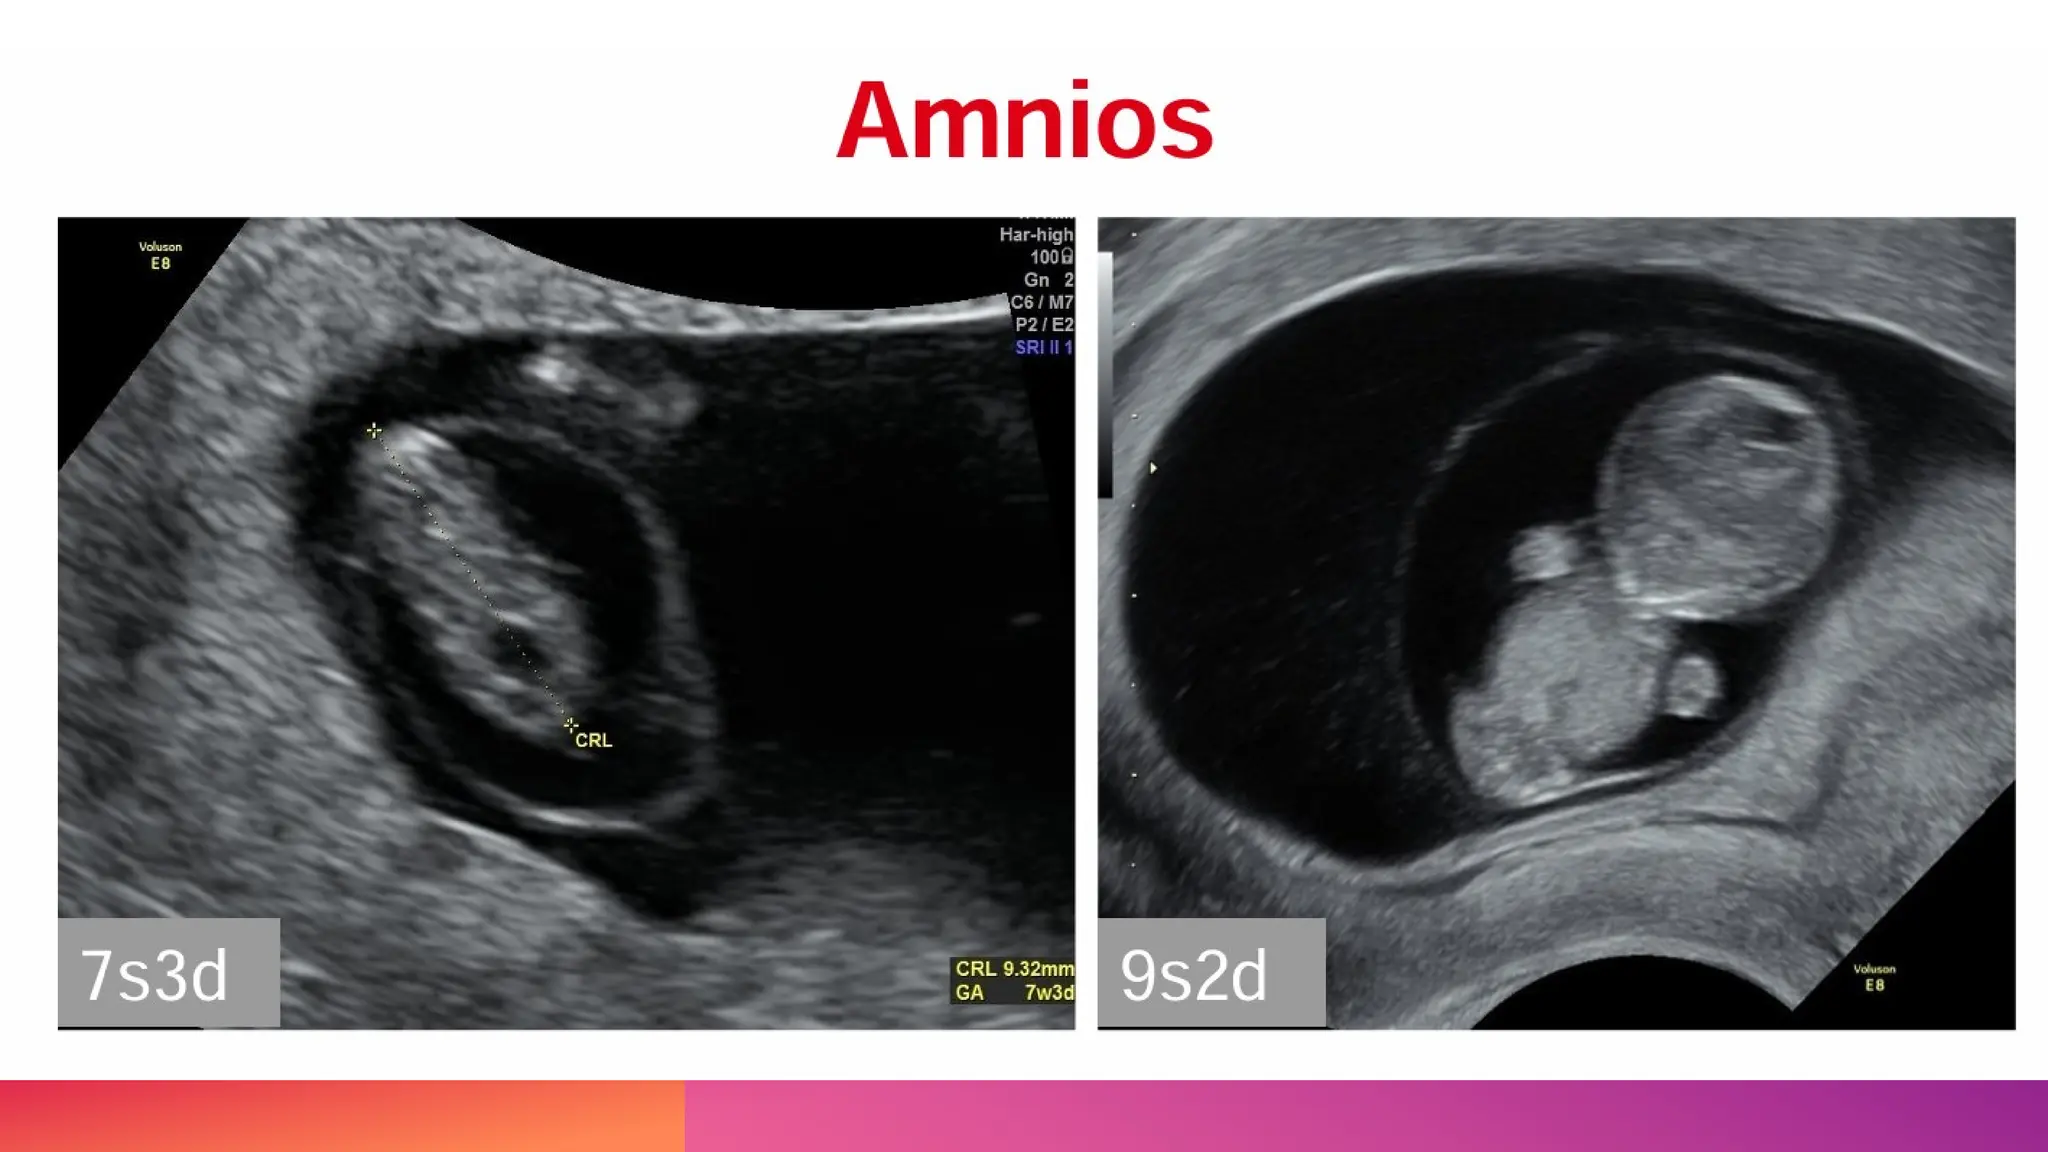

EMBRION

• Posible observar embrión de 1 a 2 mm por

ultrasonido transvaginal (polo embrionario).

• Aparece entre la 5ª y 6ª semana de amenorrea

• Aparece 2 a 4 días posterior a la detección del

saco vitelino.

• Crece a razón de 1 a 1.5 mm por día.

• Medición de la longitud cefalo-caudal. Exactiud

de 1-3 días.